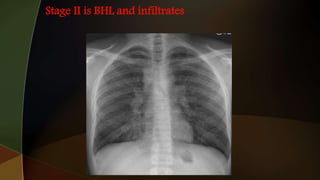

2. hilar adenopathy plus infiltrates;

1. hilar adenopathyalone 2. hilar adenopathy plus infiltrates; 3. infiltrates alone; 4. fibrosis